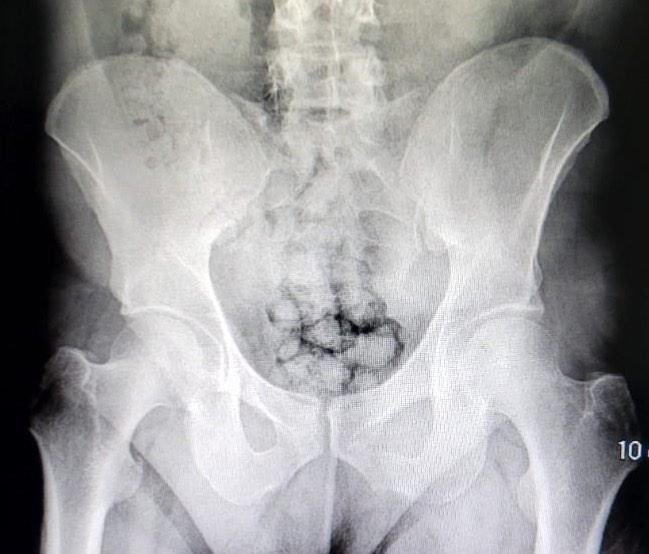

Kayseri İl Emniyet Müdürlüğü Narkotik Suçlarla Mücadele Şube Müdürlüğü ekipleri uyuşturucu madde ticareti yapan iki yabancı uyruklu şahsı takibe aldı. Ekipler, hareketlerinden ve mide bulantılarından şüphelendiği şahısları hastaneye götürdü. Burada röntgen çekinen şahısların midesinde farklı maddeler tespit edildi. Yapılan tıbbi müdahalede şahısların midelerinde sakladıkları 70 tane kapsül haline getirilmiş toplamda 500 gram metamfetamin maddesi çıkarıldı.